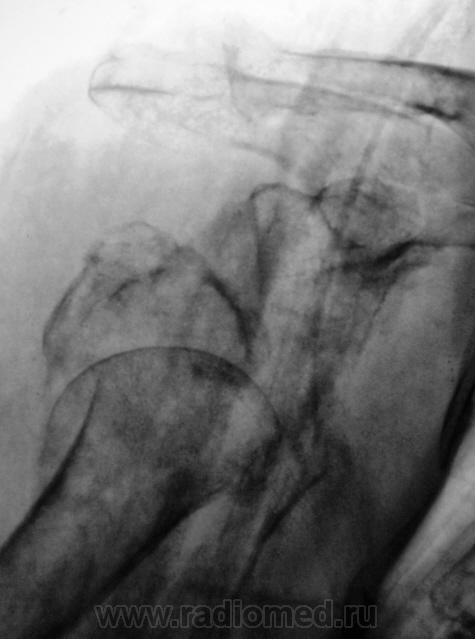

А так было до репозиции - первичный снимок.

По сравнению со снимками до репозиции определяется гипсовая повязка, в остальном - без динамики

Бесформенность между головкой и впадиной - фрагмент плечевой кости. Репозиция никакая.

Да уж.. что ж кто то не захотел идти на операцию (((